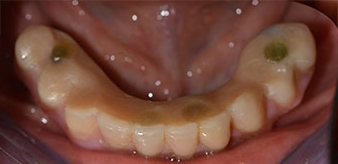

A three-dimensional cone beam computed tomography scan (CBCT, Planmeca) was performed to aid planning and minimize risks. This revealed that the quality and quantity of the available bone were sufficient for the surgery and immediate restoration using the Fast & Fixed method. Following the protocol for this concept, the implants are inserted at 35, 32, 42 and 45. Angling the distal implants by up to 45° shifts the emergence profile to posterior and generates a larger support polygon (Fig. 3).

The mental foramen was first identified as a limiting anatomical structure and then the cortical bone of the crest was smoothed with the straight handpiece and a large rose-head bur (Fig. 4).